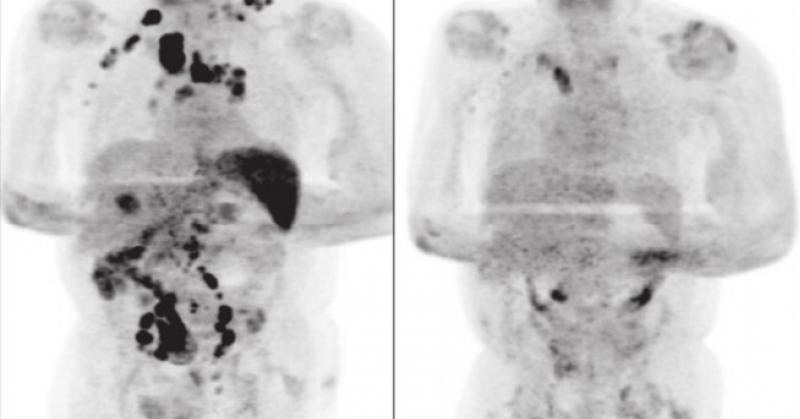

Analizan cura de paciente con cáncer tras contagiarse de Covid

Los médicos creen que las defensas inmunitarias contra el Covid-19 ayudaron a erradicar el linfoma de Hodgkin diagnosticado en el paciente.